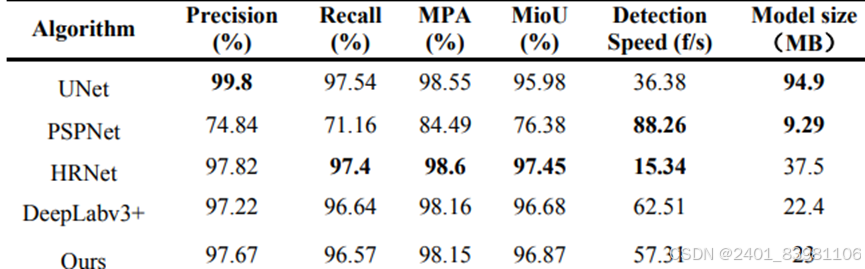

几种算法检测对比示例

- 深度学习方法:使用深度学习模型进行语义分割,如U-Net、Mask R-CNN,GraphCut,FCN2s 但如U-Net内存过大,不易部署到移动端,如下几种分割效果:

为了解决舌头拔出过程中边缘模糊和细节干扰的问题,Huang et al. 112 设计了一种使用增强型全卷积网络、编码器-解码器结构的自动舌形图像分割方法,平均灵敏度为98.97%,优于SegNet、FCN、PSPNet和DeepLab v3+四种算法

舌象边缘信息容易丢失 语义分割很难处理舌裂纹 ,精度不高

单独应用深度学习网络SBDL来提取和识别舌头裂缝 ,如图: